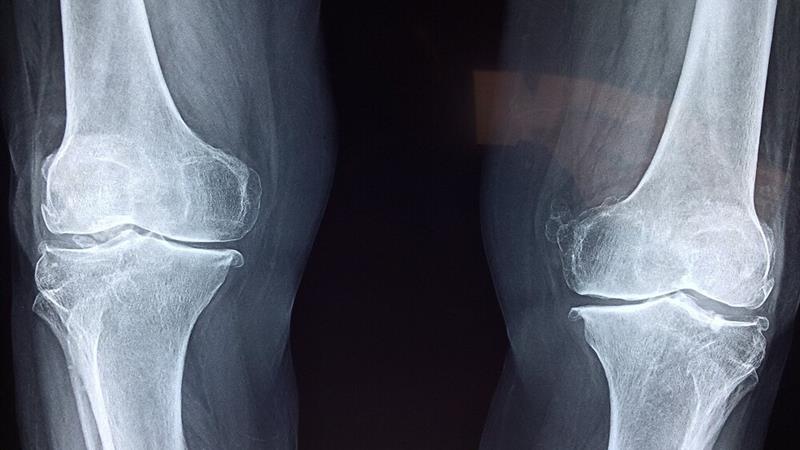

آذربانی در خصوص روشهای تشخیص بیماری توضیح داد: تشخیص پوکی استخوان با انجام سنجش تراکم استخوان (BMD) یا دگزا (DEXA) انجام میشود. این تست ساده و بدون درد، میزان تراکم مواد معدنی در استخوان را میسنجد و با کمترین میزان اشعه انجام میشود. حتی در زنان باردار نیز در شرایط خاص قابل انجام است. همه خانمهای بالای ۶۵ سال و آقایان بالای ۷۰ سال باید بدون هیچ پیششرطی این تست را انجام دهند.